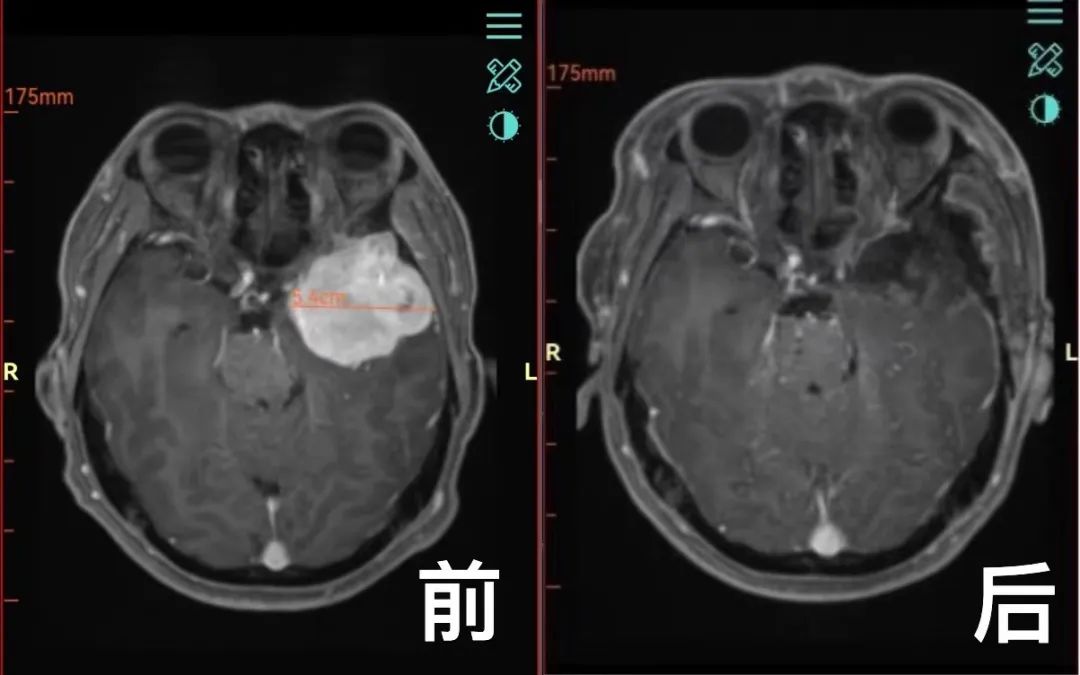

入院后,脑病一科主任钟斌组织技术团队为许师傅进行了全面的检查和评估。核磁增强等相关检查提示:“左侧颞部占位,大小约50×43×40mm,临近脑实质及脑室明显受压,中线结构偏移”。比鸡蛋还要大的肿瘤严重压迫脑部神经,导致了许先生视力下降和耳鸣。如果不及时手术,肿瘤可能会继续增大,进一步压迫脑干(生命中枢),引发头晕、头痛、呕吐、步态不稳、饮食呛咳等严重症状,甚至威胁生命。面对如此严重的病情,脑病一科钟斌主任再次组织病例讨论,制订详细的治疗方案,并与许先生及其家属进行深入的沟通。

经过系统全面的评估和细致稳妥的术前准备,钟斌主任带领技术团队为许先生进行开颅手术。经过5个多小时的奋斗,成功将许先生大脑里“鸡蛋”大的肿瘤全部切除。术后患者耳鸣立即消失,视力也明显改善,无任何神经功能障碍。更令人欣慰的是,肿瘤病理检查结果提示“良性肿瘤”,不需要进一步放化疗。许先生和家人压在心里的石头终于落了地。作为家里的顶梁柱,许先生深有感触地说:“感谢岳阳市中医医院脑病一科团队的精心治疗和护理。今后一定听从医生的指导,关注自己的健康。”